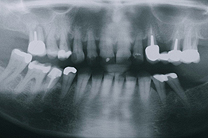

Muss ein Zahn entfernt werden, hinterlässt er eine Lücke. Diese kann mit einer Brücke wieder geschlossen werden. Eine Brücke ist ein zahngetragener, fest zementierter Zahnersatz. Sie besteht in der Regel aus zwei Kronen und einem oder mehreren Zwischengliedern. Bei einer bestehenden Lücke muss immer zwischen einer Brückenversorgung und einer Implantatlösung gut abgeklärt und abgewogen werden.